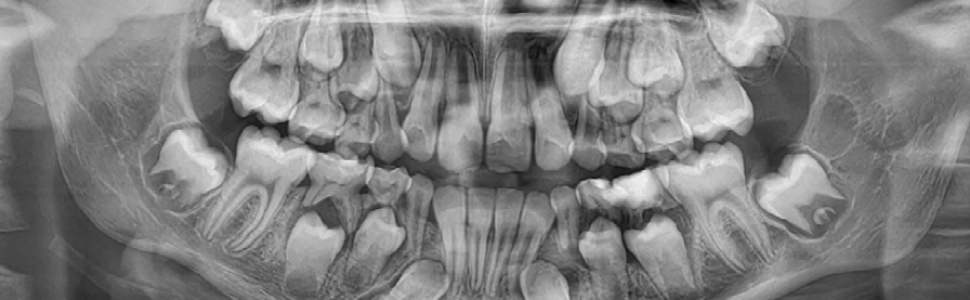

Złamania żuchwy u dzieci należą do stosunkowo rzadkich urazów twarzoczaszki, jednak ich wystąpienia wymagają szczególnej uwagi ze względu na obecność aktywnych centrów wzrostu i zawiązków zębów stałych. W pracy przedstawiono przypadek 10-letniego pacjenta, u którego doszło do obustronnego złamania trzonu żuchwy. Zastosowano leczenie zachowawcze z wykorzystaniem szynowania ortodontycznego. Przebieg leczenia i kontrola radiologiczna po 6 miesiącach potwierdziły skuteczność postępowania. Podkreślono znaczenie szybkiej diagnostyki, zachowawczego podejścia oraz regularnej kontroli u dzieci w okresie intensywnego rozwoju twarzoczaszki.

Mandibular fractures in children are relatively rare but require special care due to the presence of active growth centers and permanent tooth buds. This paper presents a case of a 10-year-old patient who sustained bilateral mandibular body fractures. Conservative treatment with orthodontic splinting was applied. Follow-up and radiological assessment after 6 months confirmed successful healing. The case highlights the importance of timely diagnosis, minimally invasive management, and regular follow-up in pediatric craniofacial trauma.